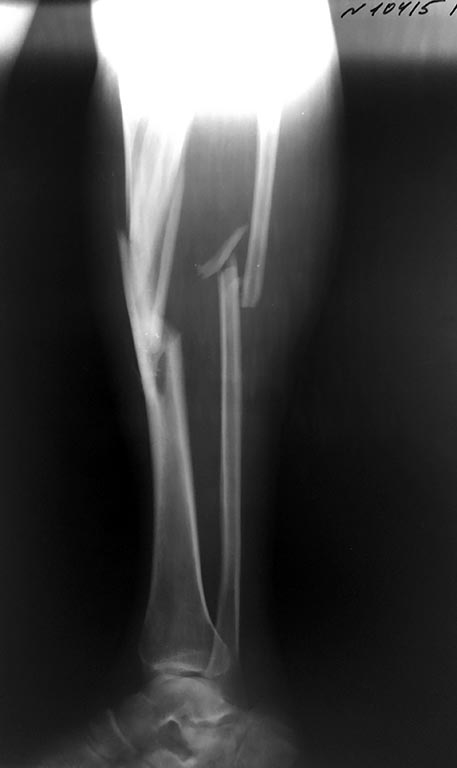

Перипротезный перелом бедра и перелом костей голени

Здравствуйте!Пациент М 54 года. 25.05.2015 г. в результате ДТП получает сочетанную травму.

Снимки прилагаются. Интересно ваше мнение по тактике лечения данного пациента. Есть многочисленные металлоконструкции и технологии оперативных вмешательств.

P.s. Прошу прощение за качество снимков.